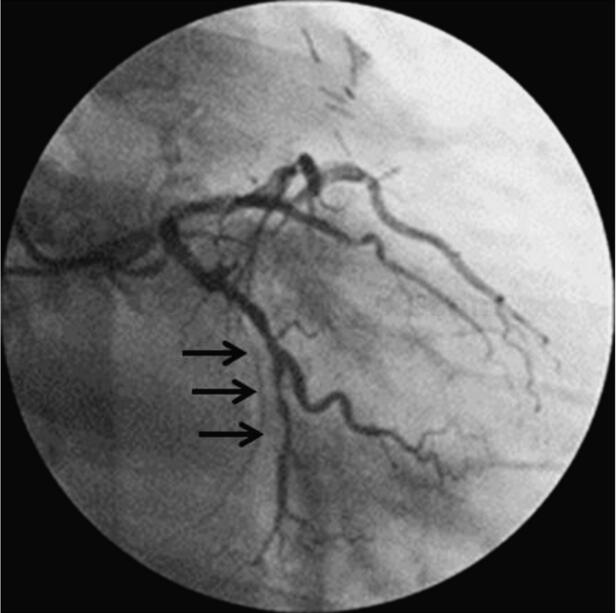

1月30日冠脉造影示:左主干远段狭窄50%,LAD开口狭窄95%,中段狭窄90%,可见血栓影像;LCX开口狭窄40%,远段节段性狭窄80%;钝缘支近段狭窄70%;RCA开口狭窄70%。患者于1月31日转至胸心外科行左内乳动脉‐前降支旁路移植手术。于2月10日行RCA开口支架置入(图068‐1~图068‐5,病变处标以箭头)。

图068‐2 RAO30°+CRA 20°

图068‐3 AP+CAU 30°